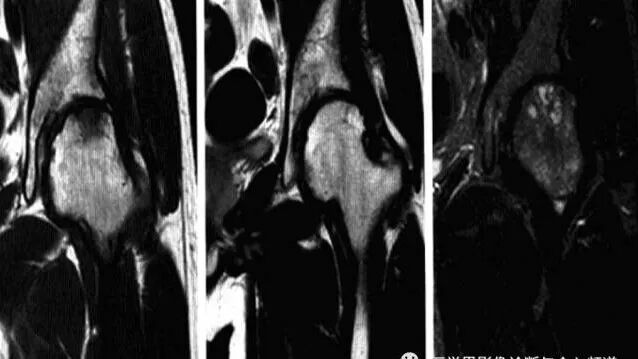

强直性脊柱炎累及髋关节

系累及中轴骨及近端大关节的血清阴性脊柱关节病。病变对称侵及骶髂关节、椎间小关节、附件韧带和近躯干的大关节,*后导致纤维性或骨性强直和畸形。髋关节是本病*常累及的关节,约占50*。

病理:表现为滑膜充血、水肿、渗出和肉芽组织增生,富含血管翳的肉芽组织向关节内延伸,由关节边缘部无软骨覆盖区开始破坏软骨及软骨下骨质,并导致纤维强直,纤维软骨化生和软骨内化骨导致骨肥大。

临床表现:多见30岁以下男性,早期下背部酸痛和僵硬不适,逐渐沿脊柱向上发展,*后出现畸形和强直。90*患者HLA-B27抗原阳性,血沉加快。

影像诊断:X线片为主要检查手段,MRI能显示早期髋关节改变。

1、平片:双侧对称受累,早期骨质疏松,关节囊膨隆,股骨头及髋臼骨质侵蚀糜烂;中期关节间隙一致性狭窄,软骨下囊性变,关节面边缘骨质增生,坐骨结节、坐骨耻骨支及股骨大转子可伴骨膜炎;晚期股骨头内移、髋臼内突,关节腔闭锁呈骨性强直。

2、CT:早期少量关节腔积液,可伴髂腰肌囊扩张,同时股骨头骨质疏松,股骨头及髋臼缘囊状、虫蚀状骨质缺损;中期关节面边缘硬化、囊变、骨赘形成,股骨头基底滑膜附着处增生,髋关节间隙均匀一致性狭窄消失,双侧髋对称性骨性强直,股骨头及髋臼可普遍性肥大。

3、MRI:①关节积液,关节间隙增宽,②滑膜增厚,增强后明显强化,③关节软骨水肿,④关节面软骨信号改变,炎性血管翳增生,信号强度不均,⑤软骨下囊性变,⑥关节骨性强直。